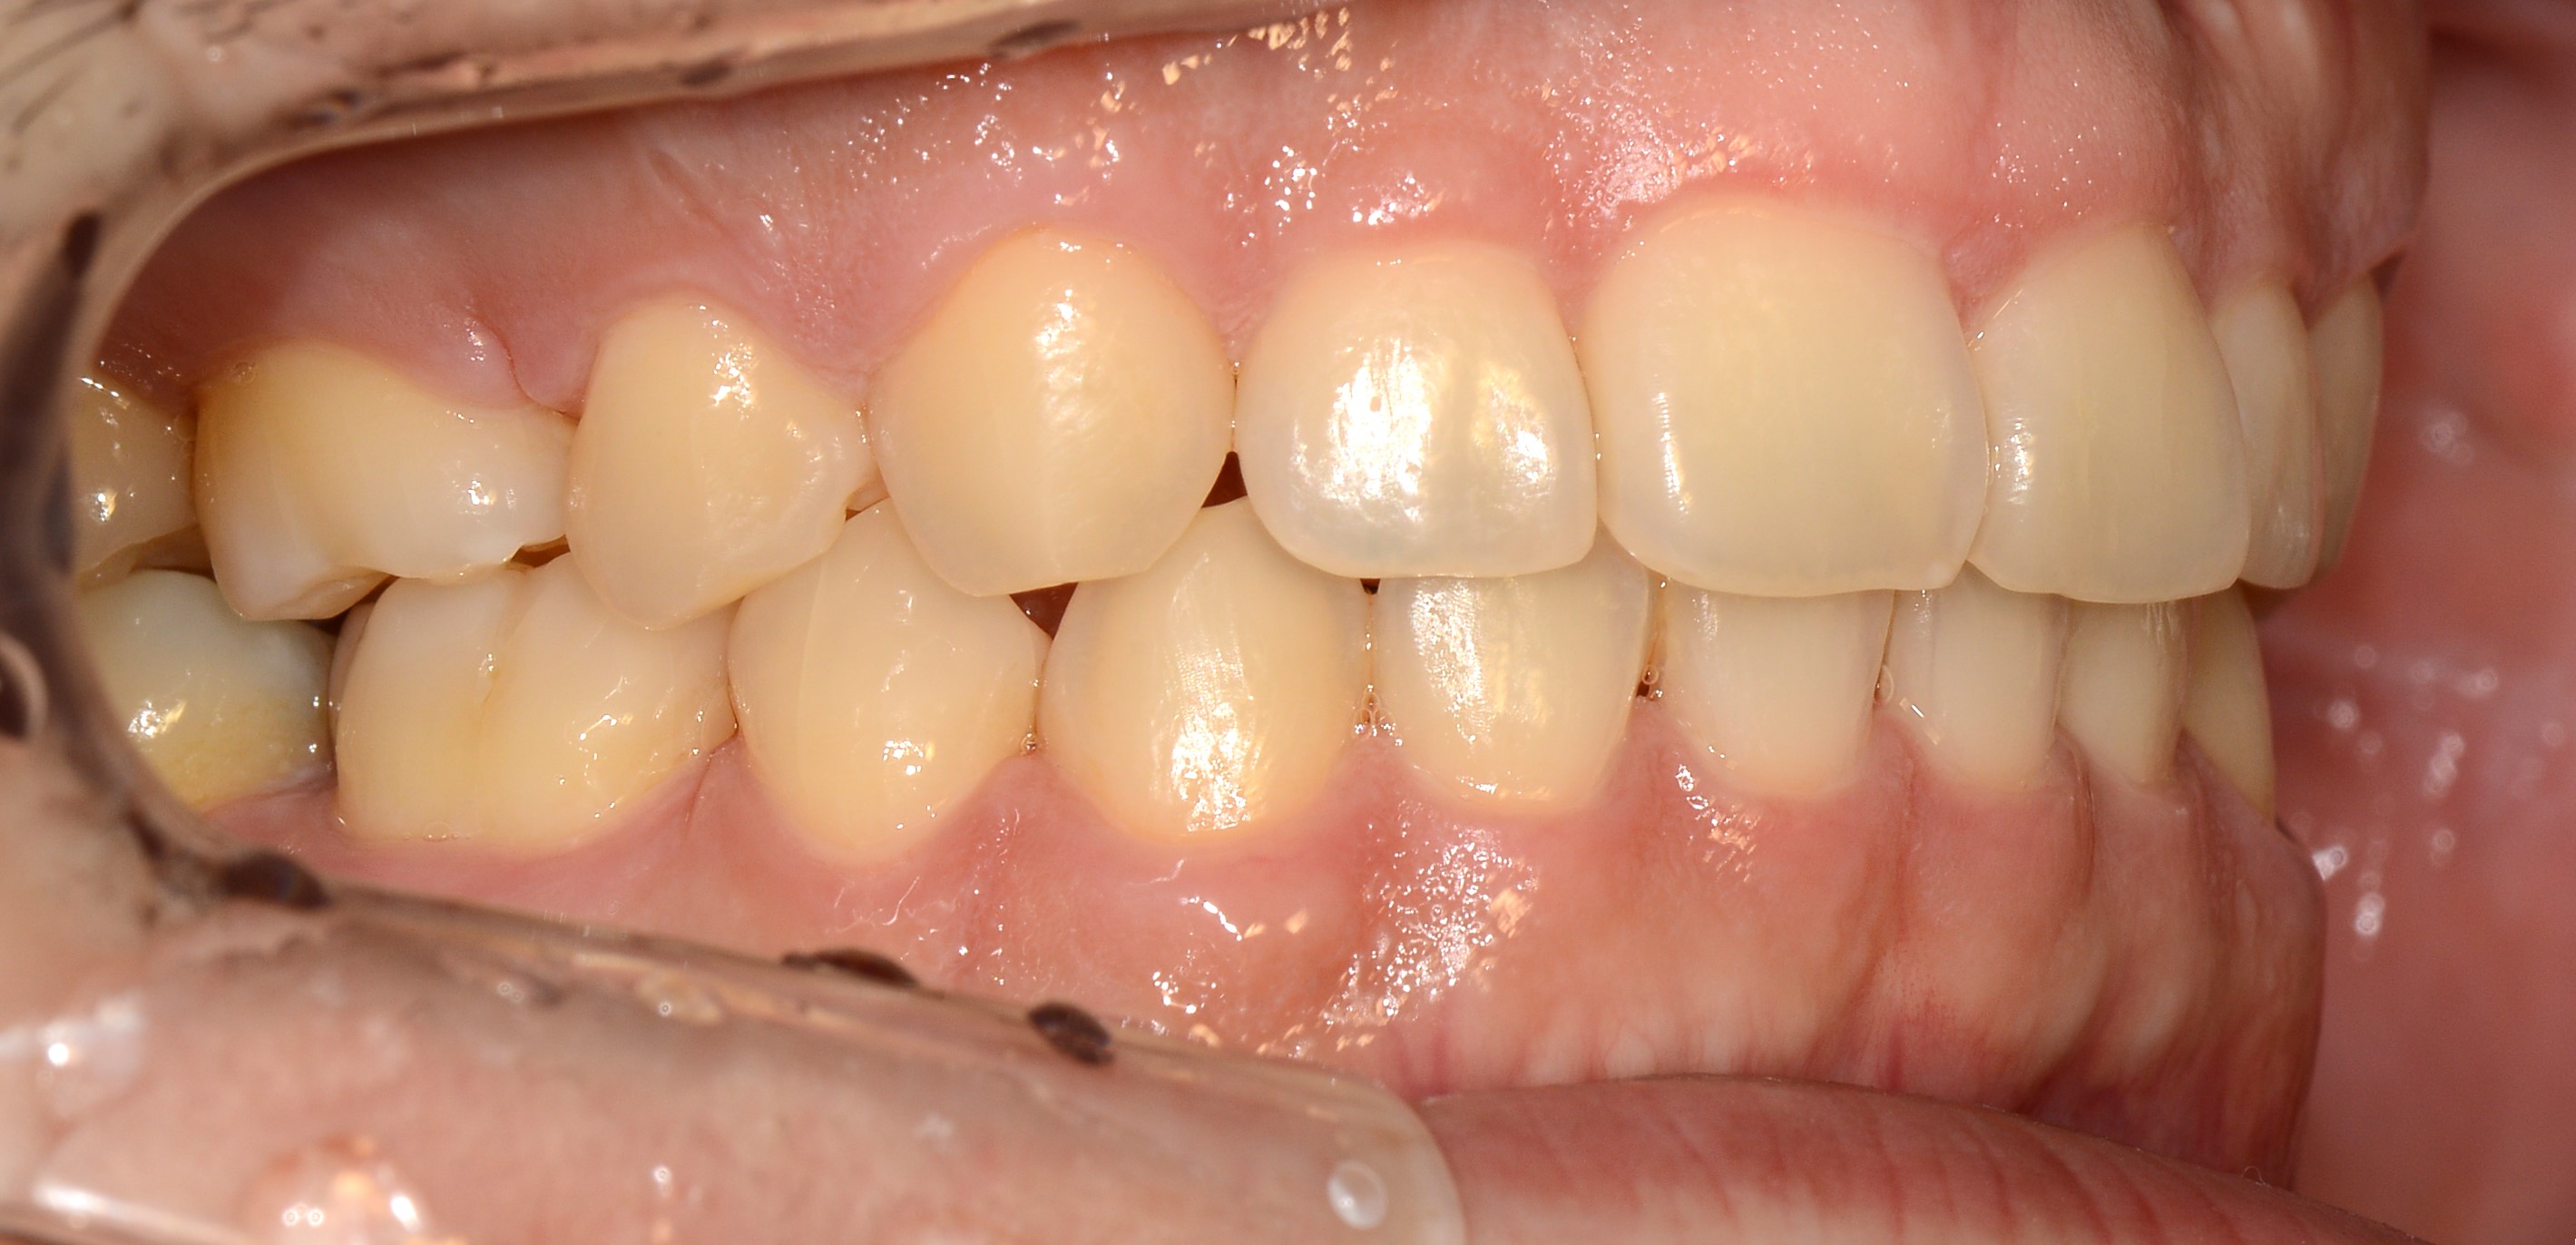

치료 전 사진입니다.